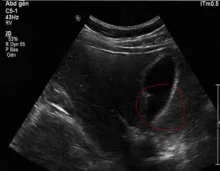

Voir les images.

Examen échographique : ci dessous, je montre 2 images d'échographie avant et après nettoyage de la vésicule biliaire, confirmant qu'il y a eu expulsion des calculs biliaires grâce à la cure d'Andreas Moritz. Ces images sont tirées des témoignages de personnes ayant pratiqué cette cure.

- Vous faîtes une échographie de contrôle juste après la cure : la vésicule ne contient plus de calculs ou en contient moins. Le médecin en profite pour vérifier la paroi de la vésicule.